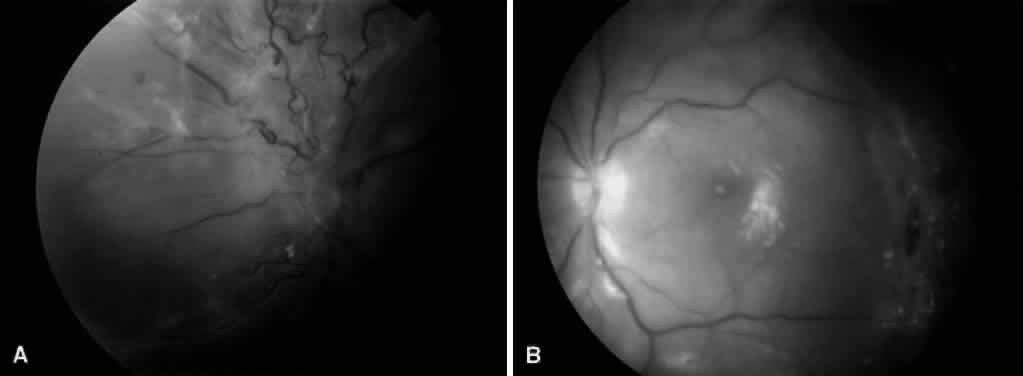

MACULAR EDEMA ASSOCIATED WITH POSTERIOR HYALOIDAL TRACTION

Fig. 6. A. Fundus photograph of an eye with vitreomacular traction syndrome. B. Fluorescein angiography showing deep, diffuse dye leakage.